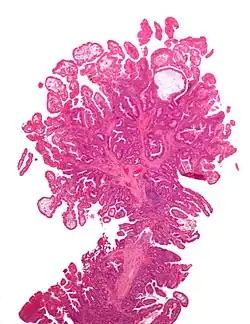

Histopalogia

Gruczolakorak jest najczęstszym nowotworem złośliwym jelita cienkiego, stanowi on około 40% zmian złośliwych tego narządu[1][6]. Pozostałe nowotwory złośliwe to rakowiak (25–40%) i chłoniaki (10–20%)[36][37][5].

Gruczolakorak najczęściej jest zlokalizowany w dwunastnicy (48%) oraz jelicie czczym (32%), rzadziej w jelicie krętym (19%)[38][39]. W dwunastnicy najczęściej jest zlokalizowany w okolicy brodawki Vatera, w jelicie czczym głównie w pobliżu więzadła Treitza (do 30 cm), w jelicie krętym zwykle jest związany z chorobą Leśniowskiego-Crohna[40]. Rak makroskopowo rośnie w formie ograniczonego nacieku lub w formie polipowatego grzybiastego tworu[41]. Przerzuty najczęściej są zlokalizowane w wątrobie (59%) lub pojawiają się jako karcynomatoza otrzewnej (25%), rzadziej występują w obrębie miednicy (5%) lub płuc (3%)[42].